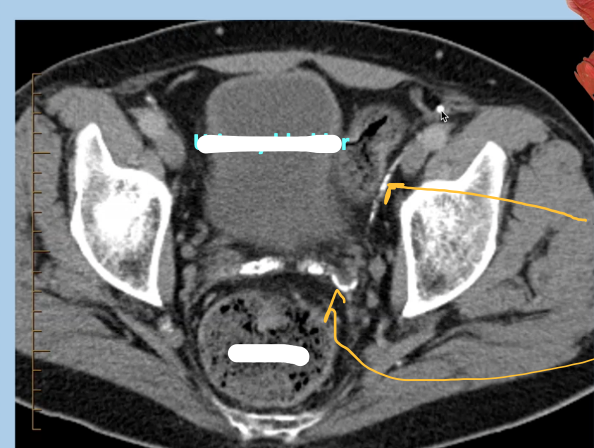

What type of imaging & view is this? And what abnormalities can we see

CT male pelvis, axial view

Calcification within the vascular structures; small bit of calcifications in vas deferes

Complete labels, what is the yellow arrow pointing to?

A

Caclification wihtin the spermatic cord

Label & what are the yellow arrows pointing to?

Yellow arrows: vas deferens running over the external iliac vessels

Ureter passes undernea this

running superior to seminal vesicles

(CT axial of male pelvis)